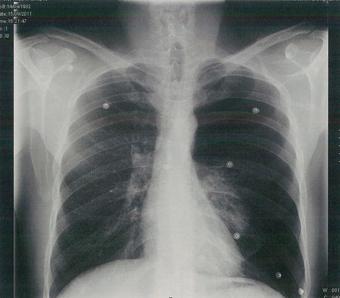

Hombre de 28 años, de 185 cm de estatura y Peso de 80 Kg, jugador de baloncesto ocasional, fumador de 5 cigarrillos día, acude al servicio de urgencias refiriendo dolor brusco en hemitórax izquierdo y ligera disnea. En la urgencia se le toman las constantes presentando TA 120/80 mm Hg, FC 80 lpm, pulsioximetría 87%, además se le ordena una radiografía de tórax (imagen nº 5). Con rcspecto al caso anterior ¿cuál es el diagnóstico más probable entre los siguientes?

RESPUESTA: 4 La pregunta expone un caso clínico compatible con un neumotórax espontaneo (los datos de dolor torácico brusco en un hemitorax acompañado de ligera disnea en un hombre joven y delgado son muy sugestivos de ello). En la RxT se aprecia además un neumotórax izquierdo con hiperclaridad del hemitorax izquierdo y pulmón izquierdo colapsado. No se aprecia derrame pleural ni neumonía (opciones 1 y 5). Asimismo el cuadro clínico no parece el de una disección aórtica (el diagnóstico tampoco se puede comprobar mediante RxT, pero tampoco existen los signos típicos de una disección) ni el de una coartación aórtica. En resumen la opción correcta es la 4.

Comentario del radiólogo:La respuesta correcta es: 4. Neumotórax. Se evidencia neumotórax masivo con atelectasia completa pulmón izquierdo.